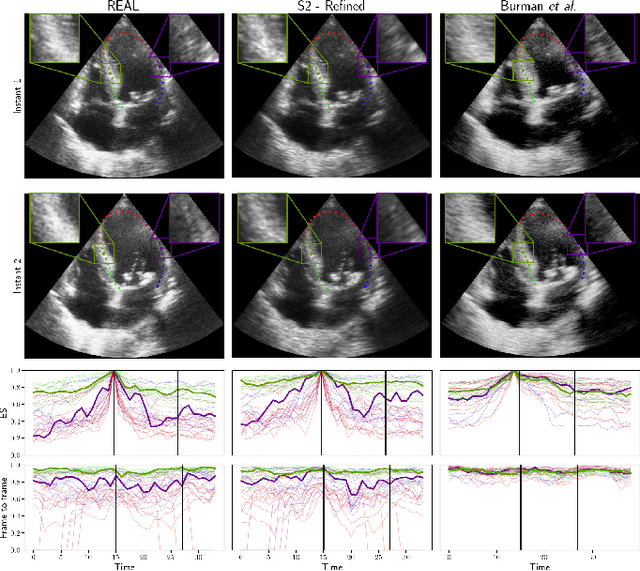

Abstract:Domain adaptation methods aim to bridge the gap between datasets by enabling knowledge transfer across domains, reducing the need for additional expert annotations. However, many approaches struggle with reliability in the target domain, an issue particularly critical in medical image segmentation, where accuracy and anatomical validity are essential. This challenge is further exacerbated in spatio-temporal data, where the lack of temporal consistency can significantly degrade segmentation quality, and particularly in echocardiography, where the presence of artifacts and noise can further hinder segmentation performance. To address these issues, we present RL4Seg3D, an unsupervised domain adaptation framework for 2D + time echocardiography segmentation. RL4Seg3D integrates novel reward functions and a fusion scheme to enhance key landmark precision in its segmentations while processing full-sized input videos. By leveraging reinforcement learning for image segmentation, our approach improves accuracy, anatomical validity, and temporal consistency while also providing, as a beneficial side effect, a robust uncertainty estimator, which can be used at test time to further enhance segmentation performance. We demonstrate the effectiveness of our framework on over 30,000 echocardiographic videos, showing that it outperforms standard domain adaptation techniques without the need for any labels on the target domain. Code is available at https://github.com/arnaudjudge/RL4Seg3D.